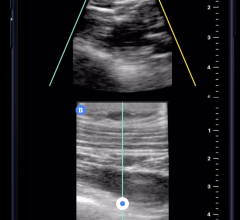

The LOGIQ e is the newest member of GE’s Compact Series of ultrasound systems. The system is designed with the speed, image quality and applications to support real-time clinical decisions in emergency settings.

It allows clinicians to view small anatomy clearly, and the system has advanced connectivity features that streamline clinical workflow by allowing clinicians to take the ultrasound exam to the patient at remote locations. With the system’s on-board image storage, it is seemingly a noteworthy imaging solution for the emergency department.